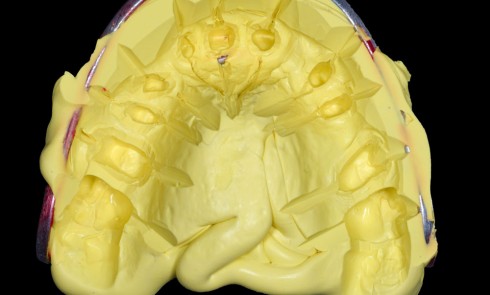

La procédure clinique est construite en deux séances. Lors de la première séance, d’une durée de 3 h, nous effectuons l’endodontie, la base intermédiaire, la préparation de l’overlay, et l’empreinte optique. La cavité d’accès réalisée est aussi petite que possible, mais aussi large que nécessaire afin de favoriser un maximum de préservation tissulaire tout en permettant un accès raisonnable aux canaux (fig. 2).

Concernant la reconstruction prothétique, nous avons réalisé une base intermédiaire avec du composite fibré afin de limiter la propagation de la fissure (Sablage, MR3, composites Flow, composite fibré, composite microhybride) [7]. On décide de recourir à un overlay de renforcement en disilicate de lithium afin de réaliser un recouvrement cuspidien pour deux raisons principales. La première étant la profondeur de la cavité d’accès, qui dépasse le plan d’inflexion de la dent et qui amplifie le risque de fracture. La deuxième étant que, de par sa préparation en biseau, l’overlay va diriger les forces occlusales principalement vers le centre de la dent et donc contenir au mieux cette fissure [8] (fig. 9 et 10).

La deuxième séance, d’une durée de 1 h, comprend l’assemblage et les réglages occlusaux.